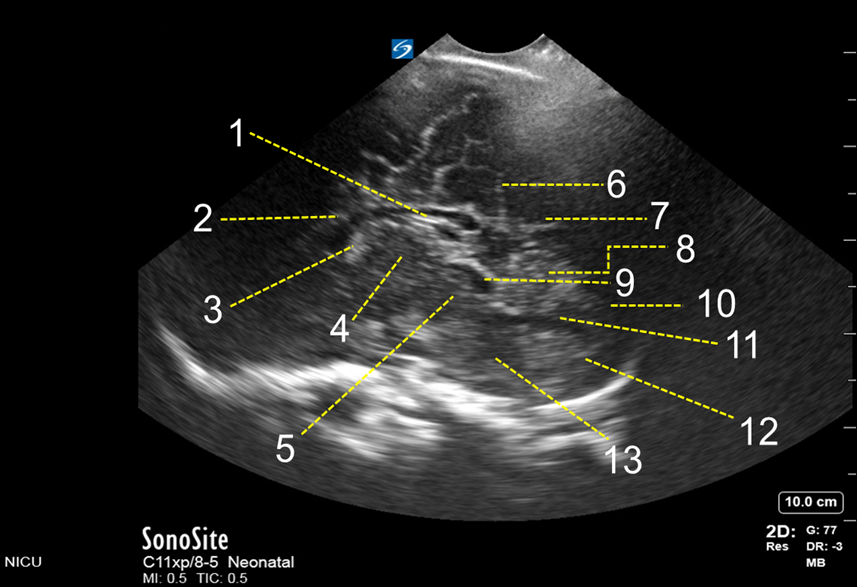

Neonatology Posterior Fontanelle Mid-Sagittal View Image

1. Tectal (quadrigeminal)

2. Corpus Callosum

3. Fornix

4. Third Ventricle

5. Mesencephalon

6. Parieto-occipital Fissure

7. Calcarine Fissure

8. Cerebellum

9. Mesencephalic Aqueduct

10. Cisterna Magna

11. Fourth Ventricle

12. Medulla Oblongata

13. Pons